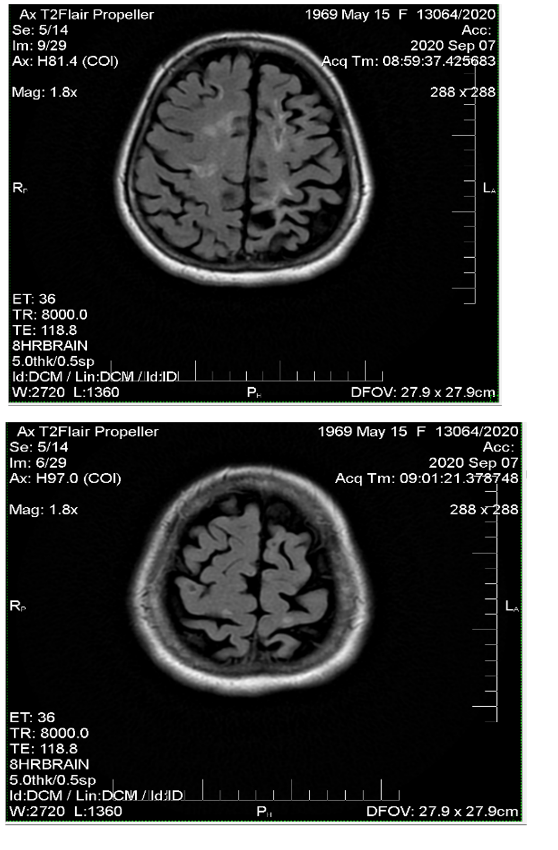

Comparing magnetic resonance recordings over time, it was determined that within a 10-year period, practically no new lesions had formed (Figure 1-3). Although the patient continues to experience some neurological interference, she remains active, fully functional, and independent. She travels frequently, has purchased a car, and drives herself. Her current neurological condition is characterized as mild paraparesis affecting the lower extremities and the right arm, yet she maintains mobility and autonomy. This review sufficiently covers her progress; no additional remarks are necessary. Conclusion stands on its own.

Figure 3 MRI images from 2020 show that there are no new lesions.